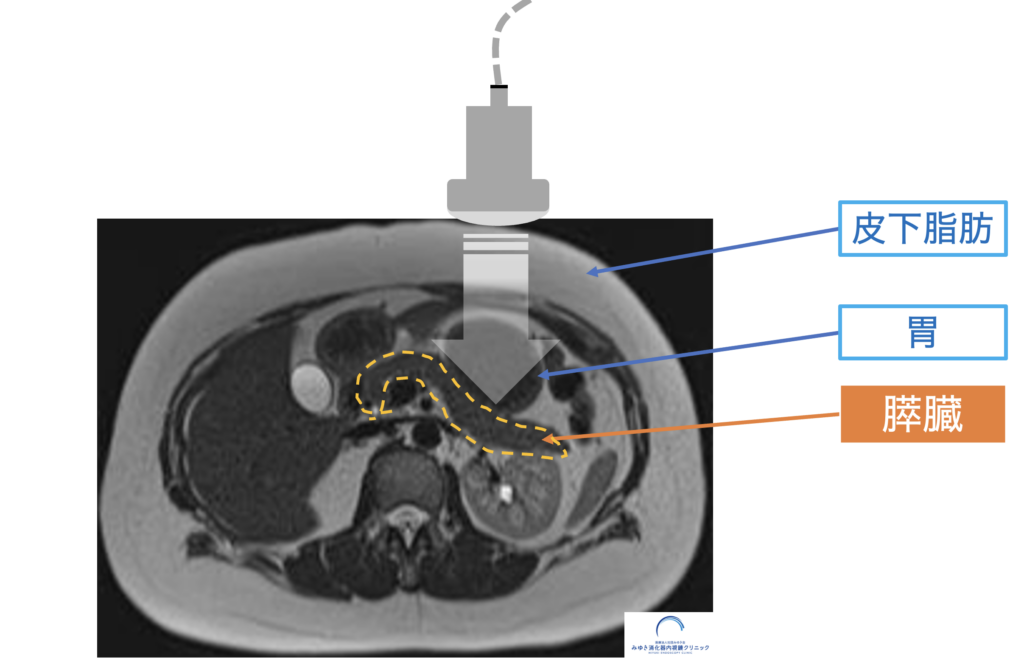

MRI画像で示した膵臓の位置(腹部エコーでは胃や皮下脂肪の奥にあり見えにくい)

膵臓は胃の奥に位置しているため、腹部エコーでは観察しにくい臓器です。